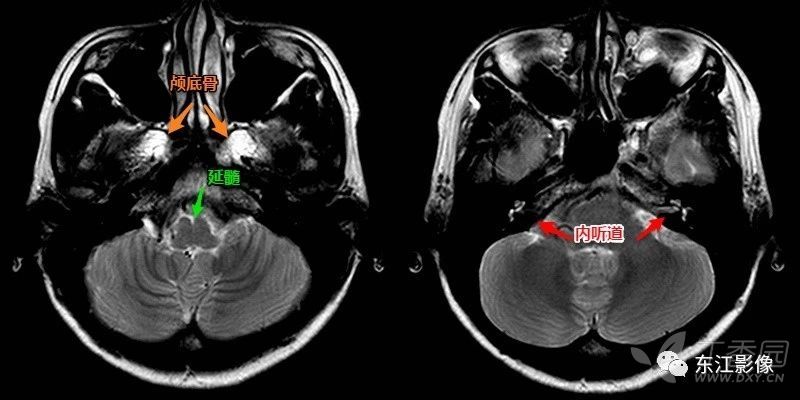

内听动脉闭塞

椎动脉颅内段是夹层动脉瘤好发区域,椎动脉闭塞也常见(图e,f).